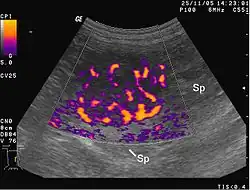

Les métastases sont souvent groupées, réalisant, lors des examens (radiographie de poumons, échographie hépatique, etc.), un véritable lâcher de ballons.